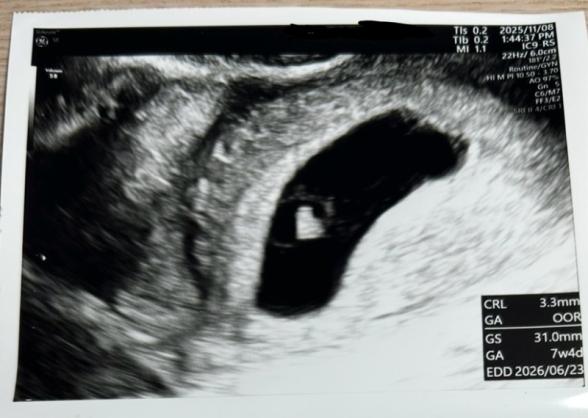

最後の生理が9/13で、10/15に妊娠検査薬で陽性反応が出ました。10/23に産科に行ったところ、生理周期が35日前後なことと胎嚢のサイズから妊娠5週目程度だろうとお医者さんから聞きました。2週間後には心拍確認できると思うよとの話があったため、11/8にまた産科に行ったのですが、胎嚢は大きくなってるけど、胎芽が10mmくらいほしいところ3mmくらいしかない。心拍も確認できない。稽留流産の可能性も考えられるから、11/14にもう一度心拍確認してみましょう。という話になりました。